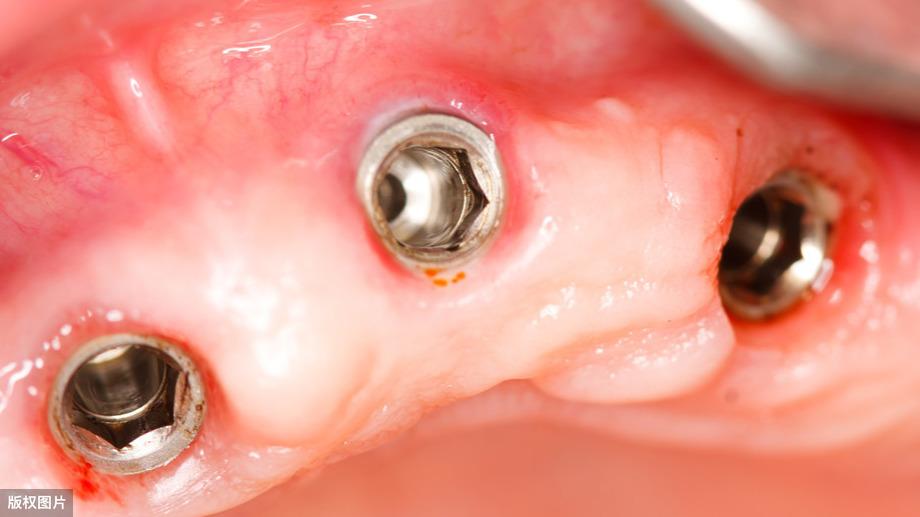

種牙后X光片,未戴冠。

通過X光片可以看到,醫(yī)生雖然盡量設計連冠種植,但還是用了十七個植體,盡管已經(jīng)是多次調整后的精簡方案,但手術時長依然長達一天。位老先生之前在另一家醫(yī)院咨詢時,醫(yī)生給的方案是種二十二個植體,光是種植費用就令人大呼“害怕”了。

這一位老先生則選擇了All-on-4種植技術,即拔即種,上下頜分別種植4個植體就完成了全口牙齒修復,費用降低了不少,而且創(chuàng)傷小,恢復快。